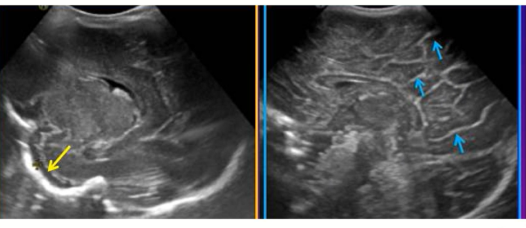

640 (1)

脑积水

640 (3)

颅内出血

640 (4)

脑室周围白质软化症

640 (5)

脑膜炎脑室炎超声